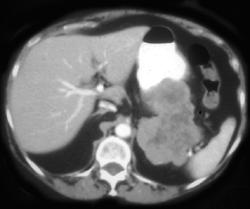

GIST Tumor